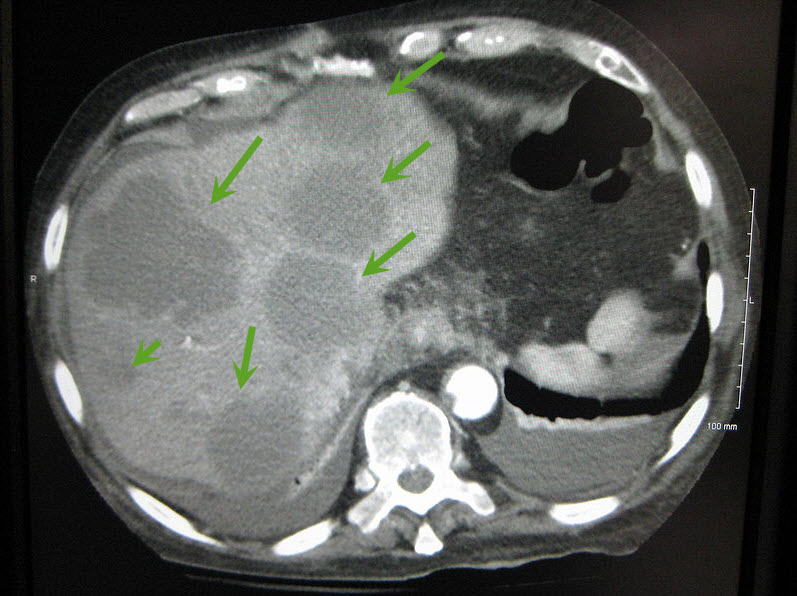

Axial CT of the abdomen showing multiple liver metastases. Image courtesy of James Heilman, MD / Wikimedia Commons / CC-BY-SA-3.0 |

The majority of liver metastases present as multiple tumors. Only 10% of all cases present with a solitary metastatic lesion. Moreover, in more than three-quarters (3/4) of patients with liver metastases, there is involvement of both lobes of the liver.